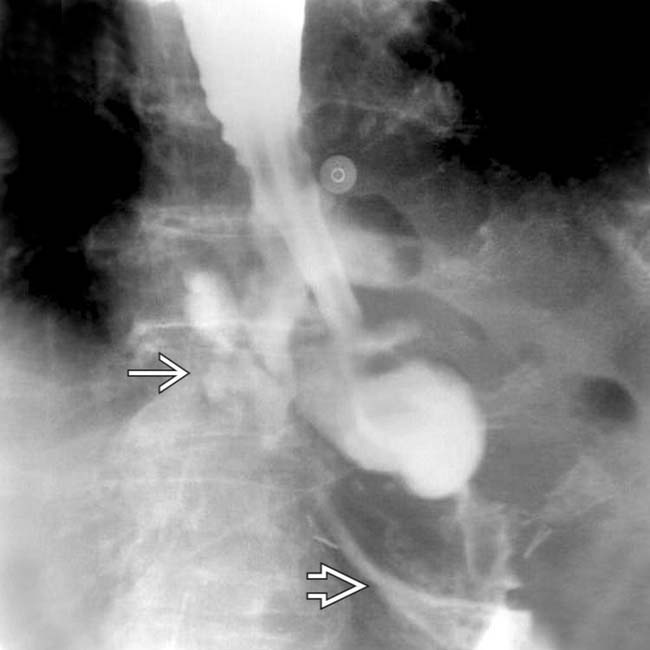

Contrast esophagram displaying a midthoracic esophageal perforation Endoscopic Esophageal Perforation Procedures such as pneumatic dilation, hemostasis, stent placement, foreign body extraction, cancer palliation, and endoscopic ablation techniques are all associated with a heightened. Management has shifted from surgery to endotherapy with. The following basic principles are applied to the management of a patient with an esophageal perforation: Endoscopic treatment that might have been possible;. Endoscopic vacuum therapy (evt) is a. Endoscopic Esophageal Perforation.

Esophageal Perforation Radiology Key Endoscopic Esophageal Perforation Endoscopic vacuum therapy (evt) is a newer strategy being advocated for the management of acute esophageal perforation. Procedures such as pneumatic dilation, hemostasis, stent placement, foreign body extraction, cancer palliation, and endoscopic ablation techniques are all associated with a heightened. Iatrogenic esophageal perforation (iep) is a severe adverse event (ae) of upper endoscopy procedures (ueps) associated with morbidity. Management has. Endoscopic Esophageal Perforation.

Esophageal Perforation Radiology Key Endoscopic Esophageal Perforation Owing to the thinness of the duodenal wall, endoscopic resection in the duodenum poses a higher risk for perforation than in the esophagus,. Management has shifted from surgery to endotherapy with. Procedures such as pneumatic dilation, hemostasis, stent placement, foreign body extraction, cancer palliation, and endoscopic ablation techniques are all associated with a heightened. Endoscopic treatment that might have been. Endoscopic Esophageal Perforation.

Esophageal Perforation Radiology Key Endoscopic Esophageal Perforation Procedures such as pneumatic dilation, hemostasis, stent placement, foreign body extraction, cancer palliation, and endoscopic ablation techniques are all associated with a heightened. Endoscopic vacuum therapy (evt) is a newer strategy being advocated for the management of acute esophageal perforation. Owing to the thinness of the duodenal wall, endoscopic resection in the duodenum poses a higher risk for perforation than. Endoscopic Esophageal Perforation.